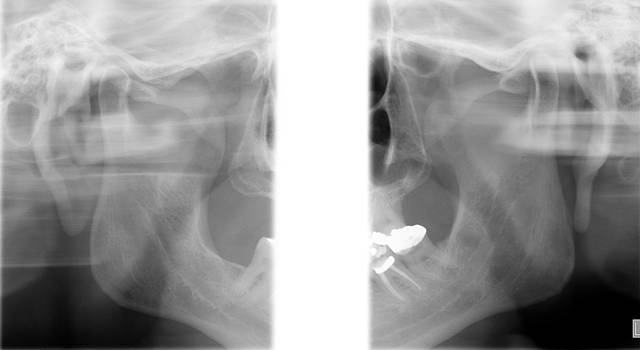

PLANIGRAFIA DE ATM

Tem a finalidade de melhor evidenciar o processo condilar em duas posições: abertura máxima (AM) e máxima interdigitação cuspidária (MIC), em ambos os lados. É especifica para análise da estrutura condilar.

* Boca Aberta

* Boca Fechada